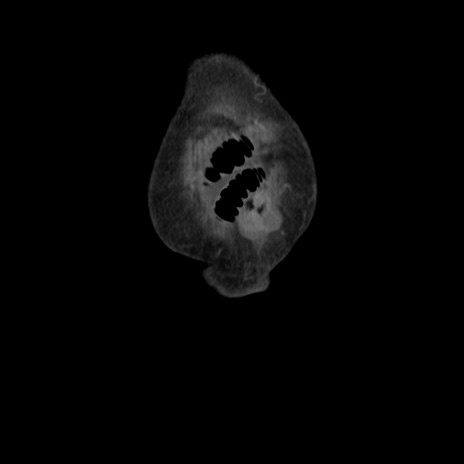

横断像